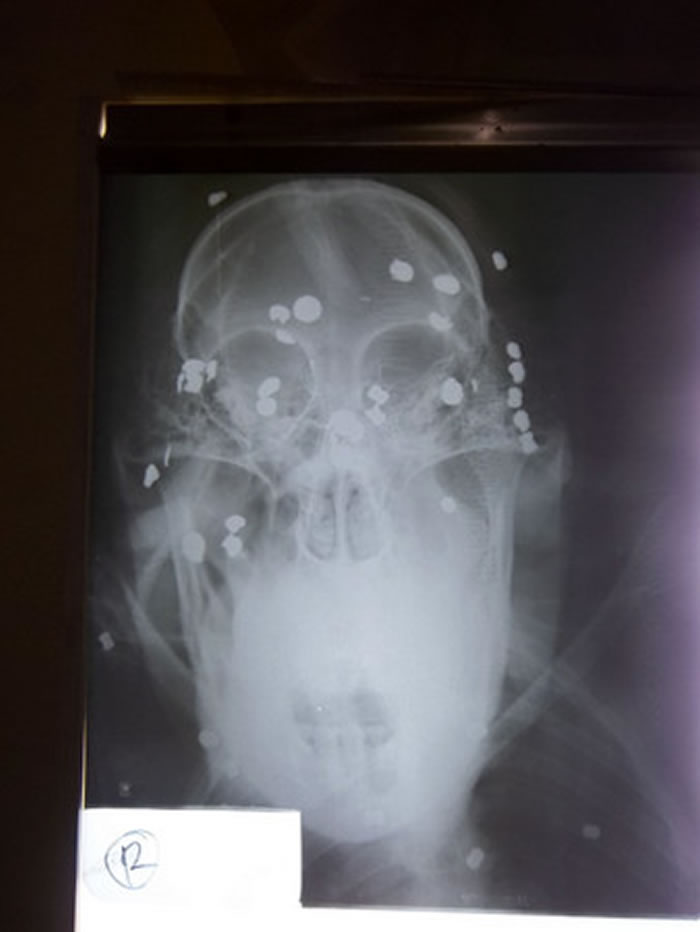

Aan体内尚残存37颗子弹

大约10岁的Aan2012年时被人发现身上有许多弹孔,照X光检查共有104颗子弹卡在体内,十分怵目惊心,经过3小时的紧急手术总共取出67颗子弹,但是还有37颗残留体内,也是造成失明的原因之一,另外听力也有受损,对于噪音太过敏感。